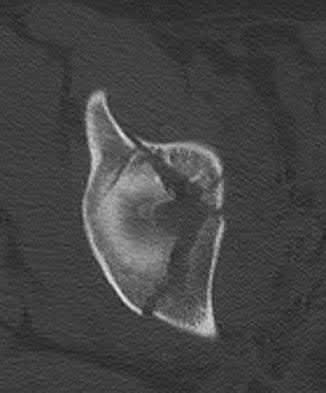

Which of the following images shows an injury pattern most consistent with a lateral compression type 3 pelvic ring injury?

Figure C is an axial CT scan of a lateral compression type 3 (LC3) pelvic ring injury.

Classically, LC3 injuries demonstrate an ipsilateral lateral compression and a contralateral APC (windswept pelvis) fracture pattern. The most common mechanism of injury in these cases is a rollover MVC or pedestrian vs. auto. LC1 injuries are characterized by an oblique or transverse ramus fracture and ipsilateral anterior sacral ala compression fracture, while LC2 injuries consist of a rami fracture and ipsilateral posterior ilium fracture dislocation (crescent fracture). While LC1 injuries can often initially be managed conservatively with protected weight-bearing and close observation, LC2 and LC3 pelvic ring injuries are almost universally operative.

Answer 1: This represents a lateral compression type 2 injury. Answer 2: This represents a lateral compression type 1 injury.

Answer 4: This represents an anterior posterior compression type 2 injury. Answer 5: This represents an anterior posterior compression type 3 injury.